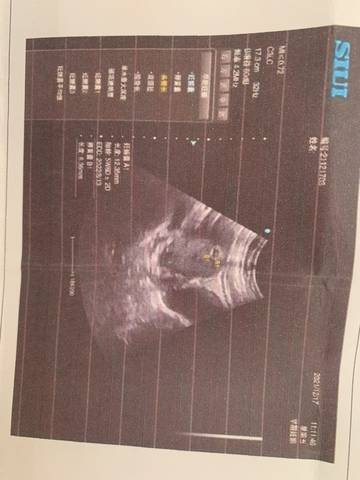

按照月经算快有两个月了,做了b超孕囊才40天左右,希望下次会有胎芽胎心了

journal_insert_pic_1682925048